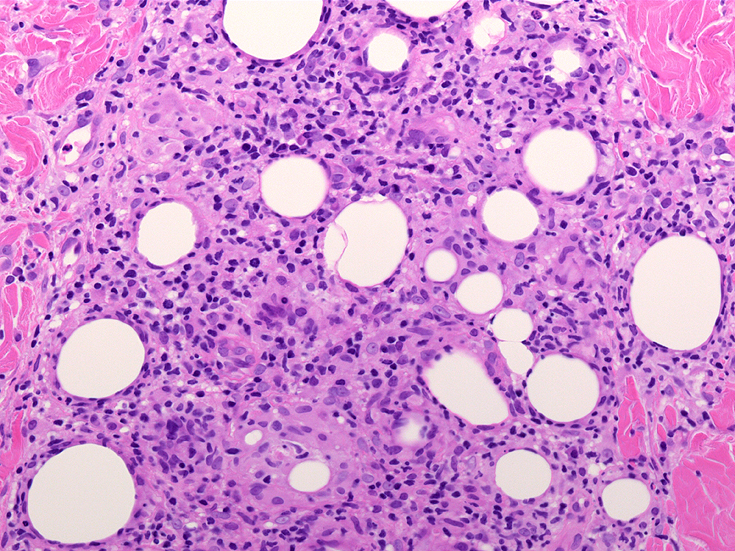

リンパ腫の定義: SPTCLは成熟細胞障害性T細胞(cytotoxic T-cell)由来で、皮下組織に脂肪識炎に似た組織像を呈しながら増殖する悪性リンパ腫。

皮下組織に優位な, 小~中型 Tリンパ球の密な浸潤が特徴。ときに大型リンパ球や組織球が混在する。 リンパ球の異型は, わずかなものから明瞭な異型を示す症例までさまざまである。